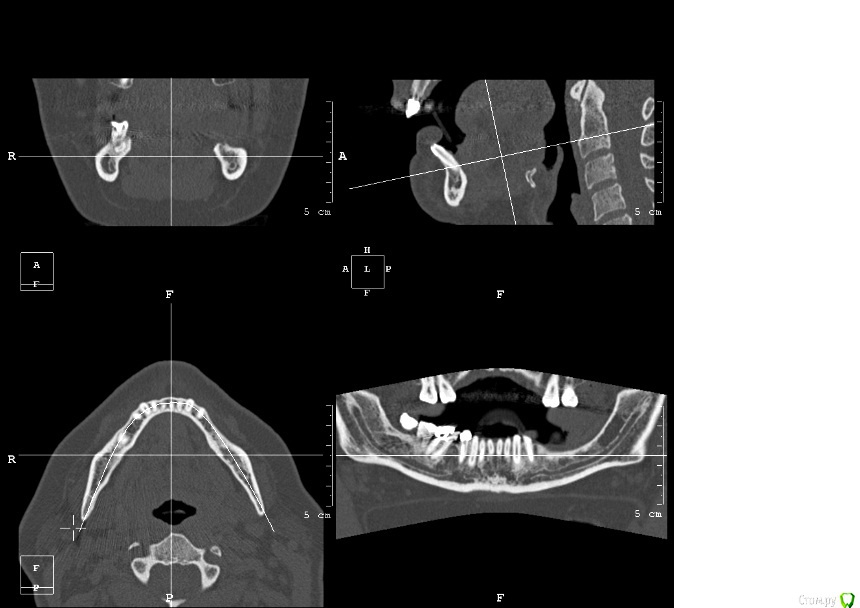

kamranchick Опубликовано 25 апреля, 2016 Поделиться Опубликовано 25 апреля, 2016 Пациентка обратилась с целью восстановления жевательного отдела.финансовый вопрос не интересует, хотелось бы чтобы с минимальными рисками.1.я думаю - удаление, 3 винта, сосидж, 5 пинов.чтобы вы предложили? Ссылка на комментарий

kamranchick Опубликовано 2 мая, 2016 Автор Поделиться Опубликовано 2 мая, 2016 ну я указал 3 сегмент, 3 винта, следовательно удаление 5 го зуба, установка имплантатов в область 35 36 и 37 Ссылка на комментарий

kamranchick Опубликовано 3 мая, 2016 Автор Поделиться Опубликовано 3 мая, 2016 Тут 2ух этапно я пошёл, сначала НКР Ссылка на комментарий